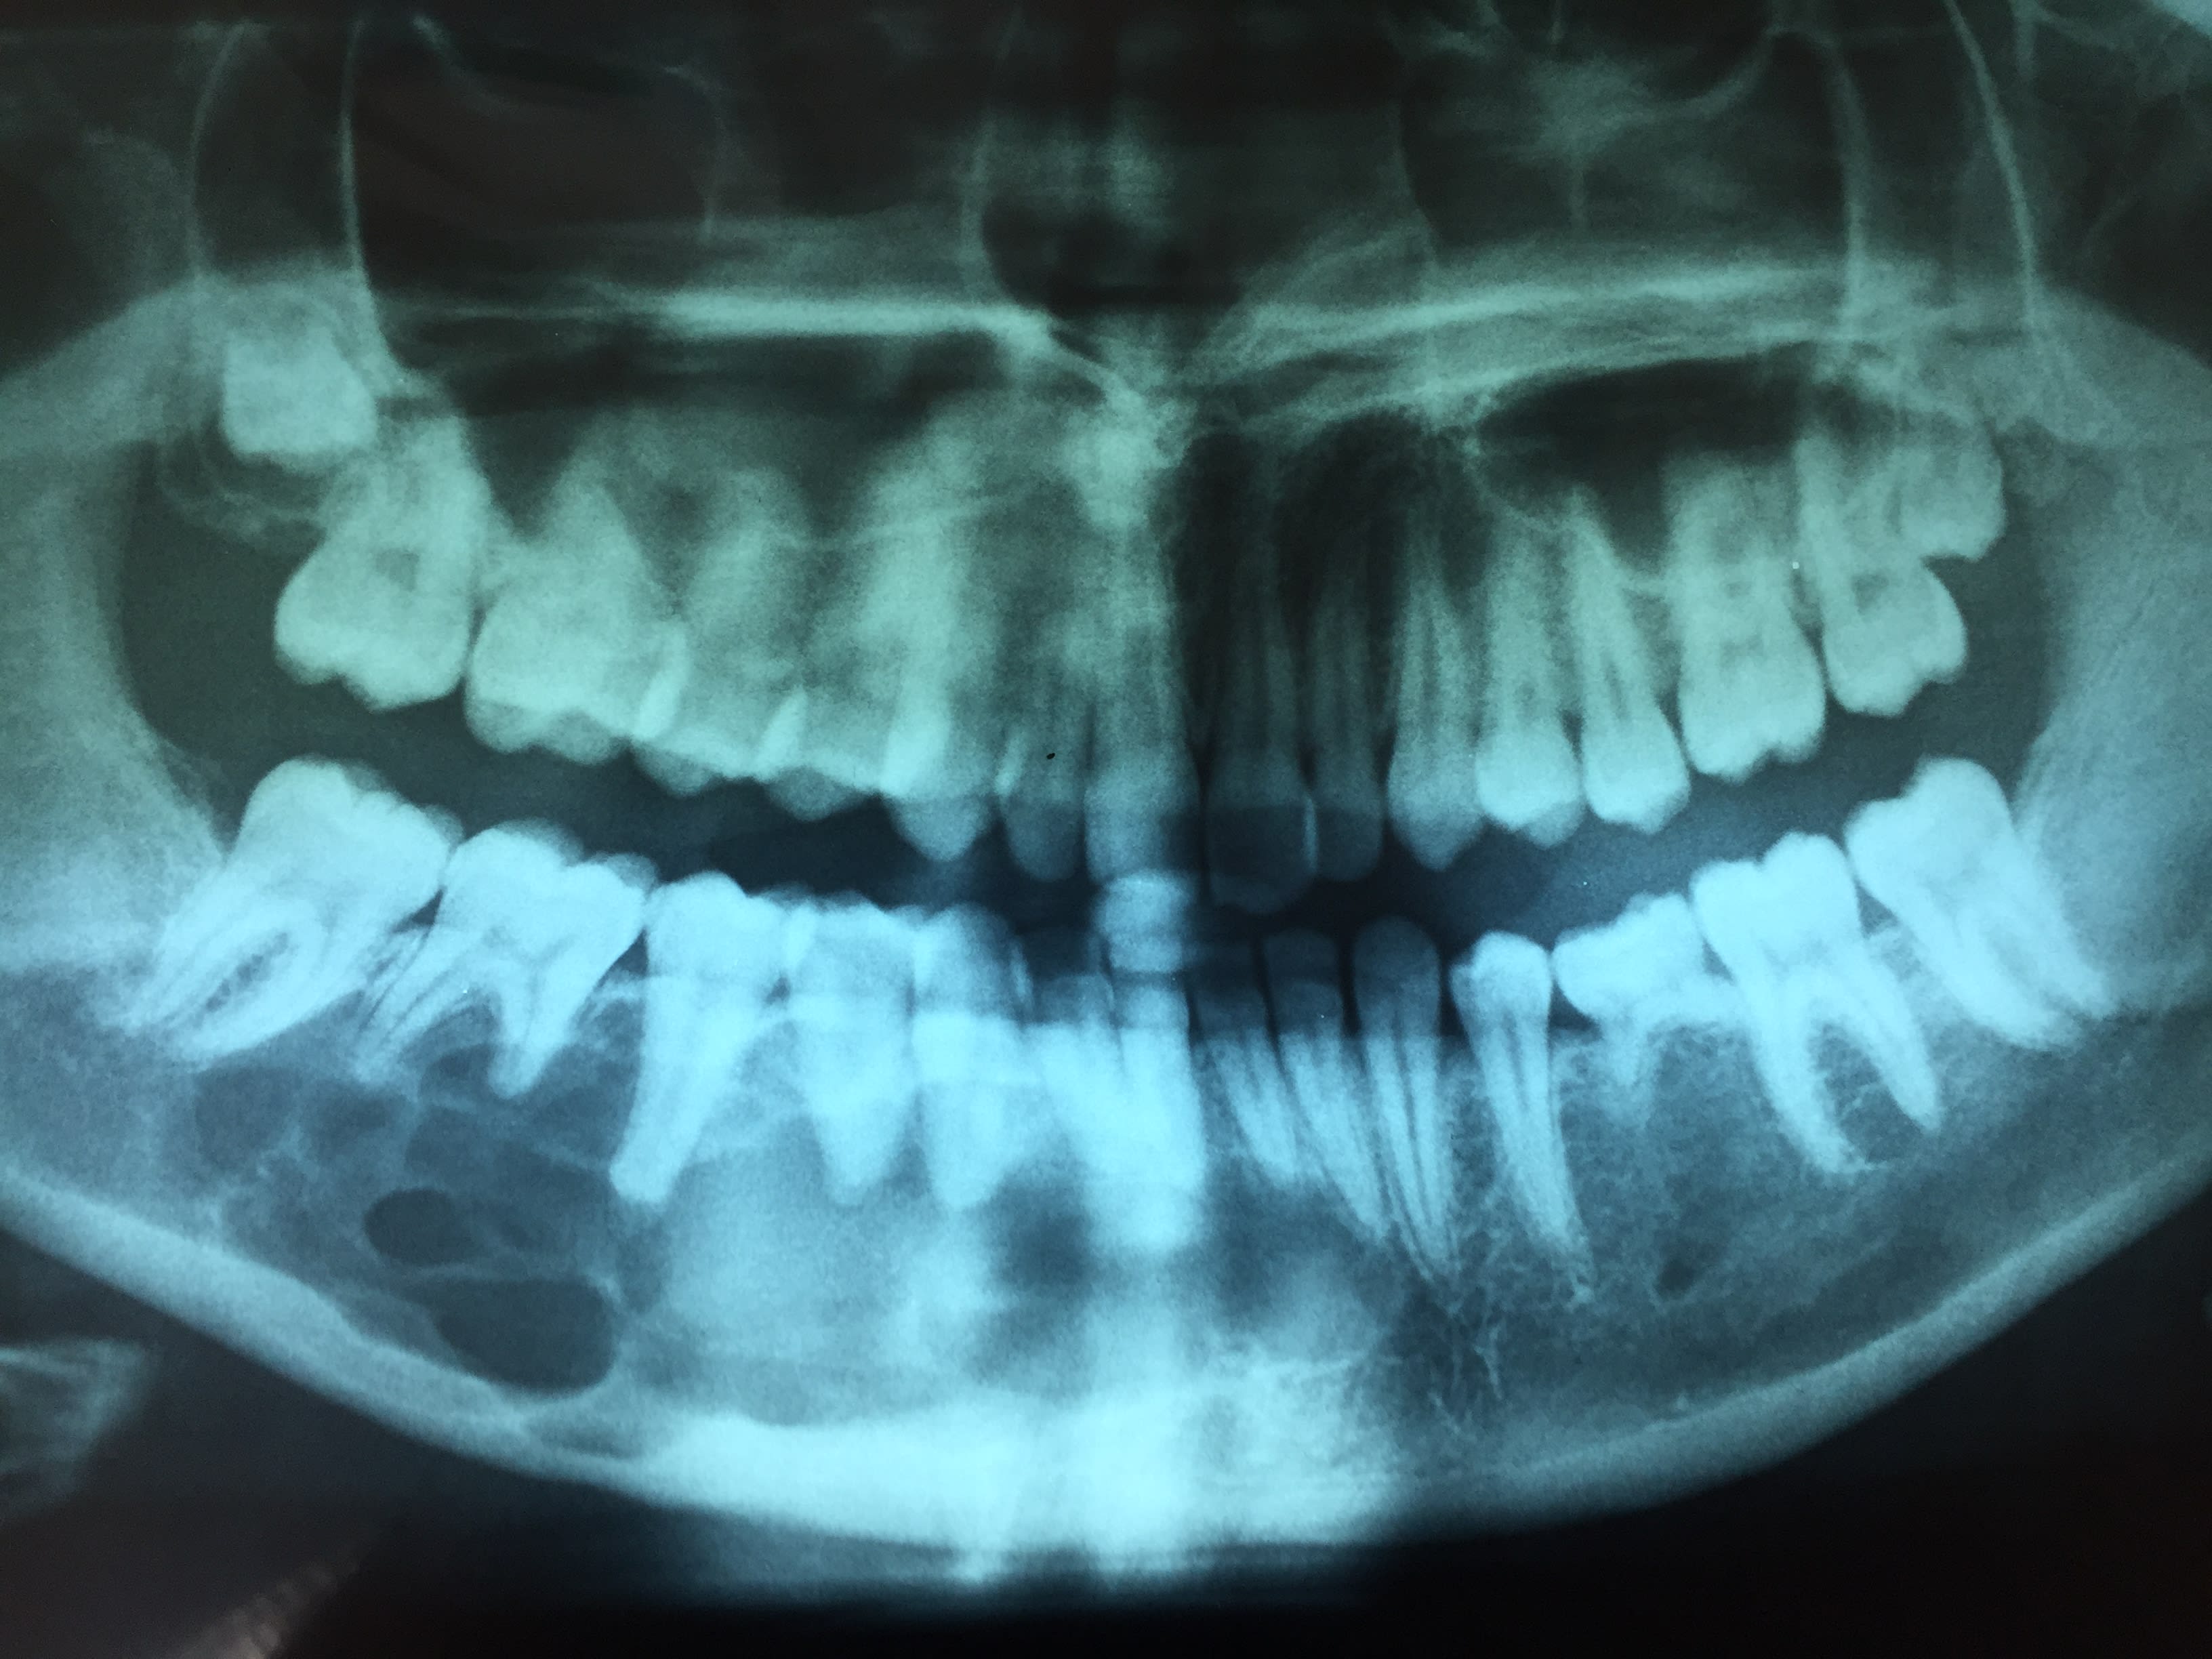

Jeune fille de 21 ans , ortho il y a 5 ans qui ressent une "boule" sous mandibulaire sans autres symptômes.

La radio vous inspire quoi ?

multilobe: ici en effet un améloblastome. Tu adresses en maxillo faciale.

Et oui sans doute un améloblastome , dit si mes souvenirs sont bons multikystiques . Attention je n'ai rien contre les orthos , mais j'ai la haine contre celui ci car la radio date déja et qu'elle a été effectué comme controle et qu'il n'a rien remarqué . La gamine venait juste me demander conseil pour une 22 qui part en sucette ;o((((

Quelques news de ma patiente , c'est bof quand même avec une extension sur le secteur 30 , a priori j'aurai tablé sur le trou mentonnier , mais à bien y regarder sur la pano d'origine y a comme qui dirai un doute ?

Non non, la lésion est bien visible de mésial de 33 à 47

Le chir en per opératoire pense plus à un keratokyste mais il attend l'anapath , en cas d'ameloblastome il y aura reintervention .